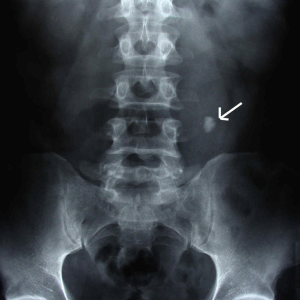

Whole pelvic radiation therapy improves survival in high-risk prostate cancer

Prostate cancer (PCa) patients with higher lymph node (LN) risk scores and Gleason grade who are treated with whole pelvis radiotherapy (WPRT) have better overall survival (OS), reports a study.